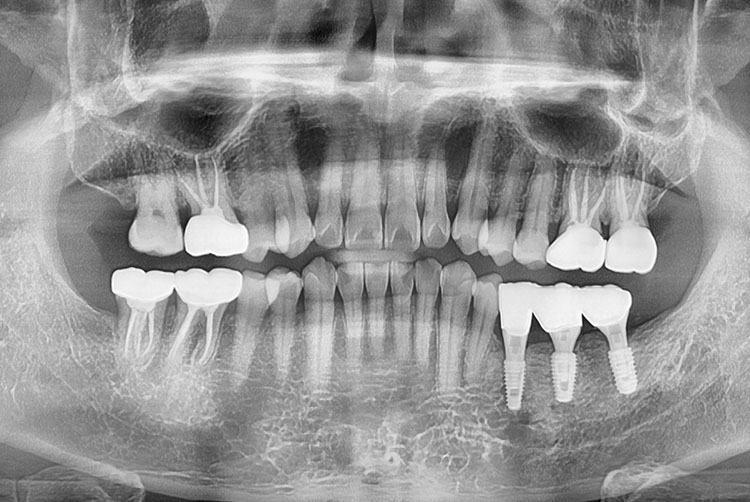

[임플란트] 임플란트

치료전 : 2016-02-20

치료후 : 2021-10-20

세종치과는 많은 환자와 다양한 케이스를 바탕으로 항상 편안한 임플란트 수술을 제공하고자 노력하고,

오래동안 튼튼히 쓸 수 있는 임플란트 수술을 가장 큰 목표로 삼고 있습니다